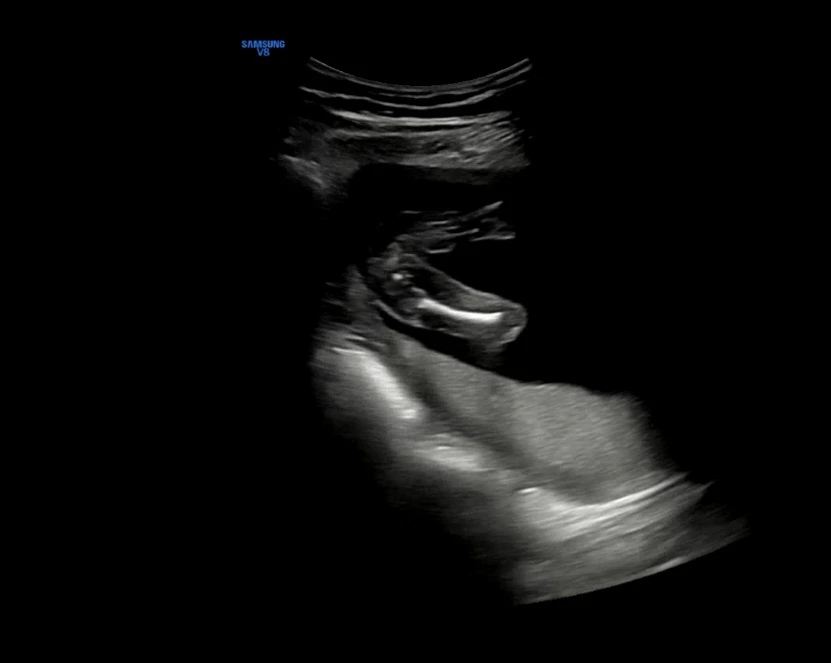

임신 17주차 초음파 사진

한 달이 아닌 한 주 후에 다시 병원에 갔다. 두 번째 초음파 사진처럼 양쪽 다리에 아무 것도 보이지 않는 것처럼 우리 집에는 딸이 찾아왔다 :) 16주차와 또 다르게 더욱 사람의 모습을 하고 있는 반짝이! #임신17주초음파